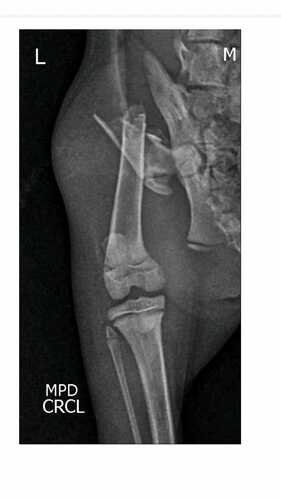

Olá sou a Gaia, tenho 3 meses adoro ronronar, sou muito dengosa e sapeca; no último domingo (04/02) fui atacada por um cachorro que entrou na minha casa, fui salva pelo meu dono e minha irmã canina, mas fui muito machucada, me levaram correndo para a tia veterinária que fez analgesia e um raio-x pra ver o que aconteceu com minha patinha e infelizmente ela foi quebrada, preciso de uma cirurgia para voltar a pentelhar todo mundo e infelizmente meu tutores não conseguem arcar com o valor; ficaria muito feliz com qualquer ajuda! Muito obrigada!